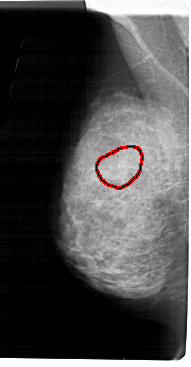

A_1939_1.LEFT_MLO

LEFT_MLO LINES 5491 PIXELS_PER_LINE 2851 BITS_PER_PIXEL 12 RESOLUTION 43.5 OVERLAY

FILE: A_1939_1.LEFT_MLO.OVERLAY

TOTAL_ABNORMALITIES 1

ABNORMALITY 1

LESION_TYPE CALCIFICATION TYPE AMORPHOUS DISTRIBUTION SEGMENTAL

ASSESSMENT 4

SUBTLETY 3

PATHOLOGY BENIGN

TOTAL_OUTLINES 1

BOUNDARY